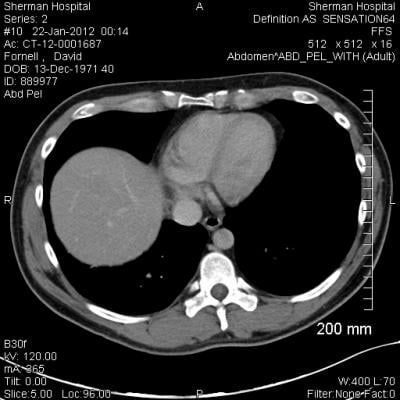

The research is the largest study to date to use radiomics — extracting statistical information from images and other measurements — to help predict the likely progression of cancer or its response to treatment based on positron emission tomography (PET) scans of patients with non-small-cell lung cancer and head and neck cancer.

In the study, researchers performed positron emission tomography (PET) scans in 163 non-small cell lung cancer patients and 174 head and neck cancer patients before and after treatment. They extracted a variety of information from each tumor, including the intensity value of the PET image, the roughness of the image and other information, such as how round the tumor was. In PET, the brighter an area is, the higher the intensity, showing that the tumor is consuming a greater amount of energy from the injected radioactive glucose substitute tracer.

Comparing the information gleaned from the before and after scans to how the patient fared — including whether the tumor shrank or how long the patient survived — researchers can create models that will help direct future therapy. For example, in the study researchers determined that lung tumors that have a higher uptake of the tracer need to be treated with a higher dose of radiation than is typically prescribed.

“Standard protocol today is to only use PET imaging to define the extent of a tumor to be treated,” said Deasy. “Based on the information from this study, the data would be extracted from those images and put into models that would tell the physician what dose was required to kill the tumor with a high probability.”